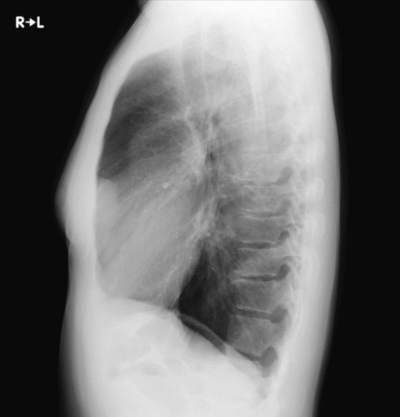

23歳の女性。入社時の健康診断の胸部エックス線写真で異常陰影を指摘されたため産業医から紹介受診となった。自覚症状はない。喫煙歴はない。胸部エックス線写真を別に示す。

次に行うべき検査はどれか。2つ選べ。